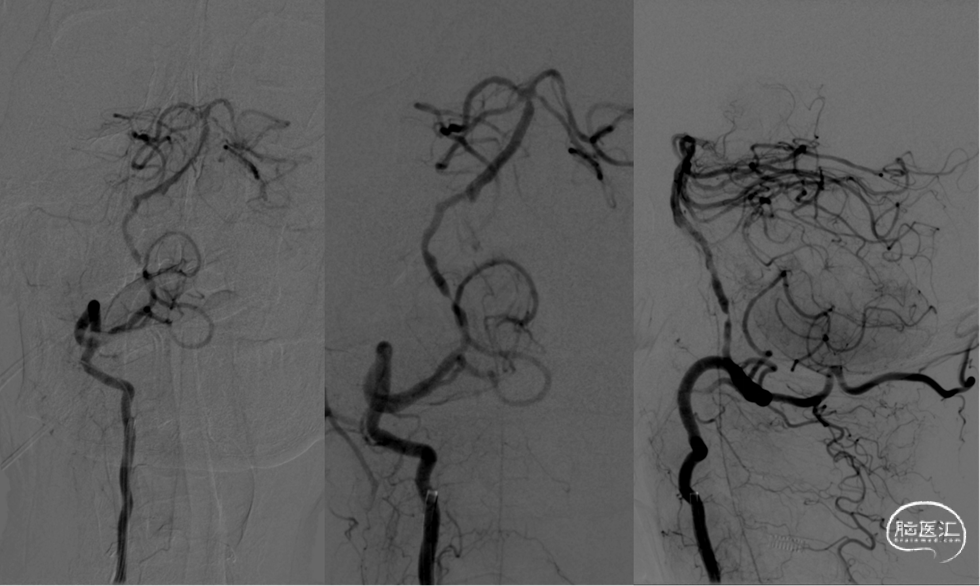

手术方案:全麻下行右侧椎动脉V4段血管成形术(Gateway球囊预扩张后置入Neuroform EZ自膨式支架),

300cm微导丝携Gateway球囊到位,行球囊扩张及预扩张后造影。

1、本例患者反复出现神经功能障碍,血管评估提示双侧椎动脉V4段均为重度狭窄,左侧狭窄位置位于发出小脑后下动脉下方,紧邻小脑后下动脉,同时左侧小脑后下动脉起始段存在有重度狭窄,相对粗大。

2、右侧椎动脉V4段血管狭窄附近未见有明确血管分支,因此手术选择了行右侧椎动脉V4段球囊扩张及支架置入术,因双侧椎动脉V4段狭窄以远椎动脉及基底动脉汇合处血管良好,因此右侧椎动脉V4段狭窄处支架置入术后病人右侧椎动脉及远端基底动脉血流明显改善外,同时也可见到左侧椎动脉V4段逆向显影至左侧小脑后下动脉。同时避免了左侧椎动脉支架置入术中对左侧小脑后下动脉的影响导致小脑后下动脉缺血事件发生的可能。

3、Gateway球囊为半顺应性球囊,推送性能良好,术中缓慢扩张,可减少球囊移位、血管变形及夹层等,为后续支架置入提供了良好的条件。

4、EZ支架通过性好,释放顺畅,径向支撑力强,支架贴壁良好。